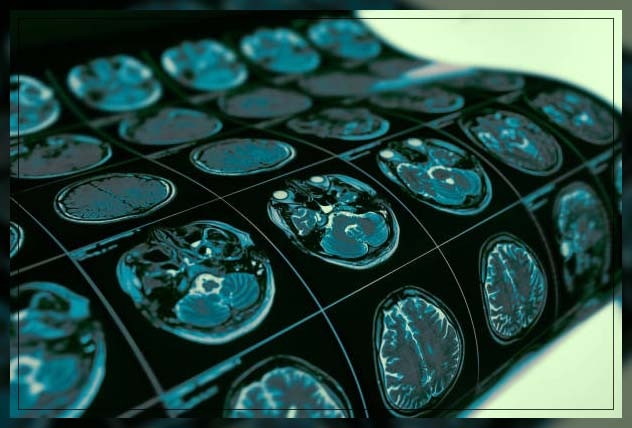

dementia